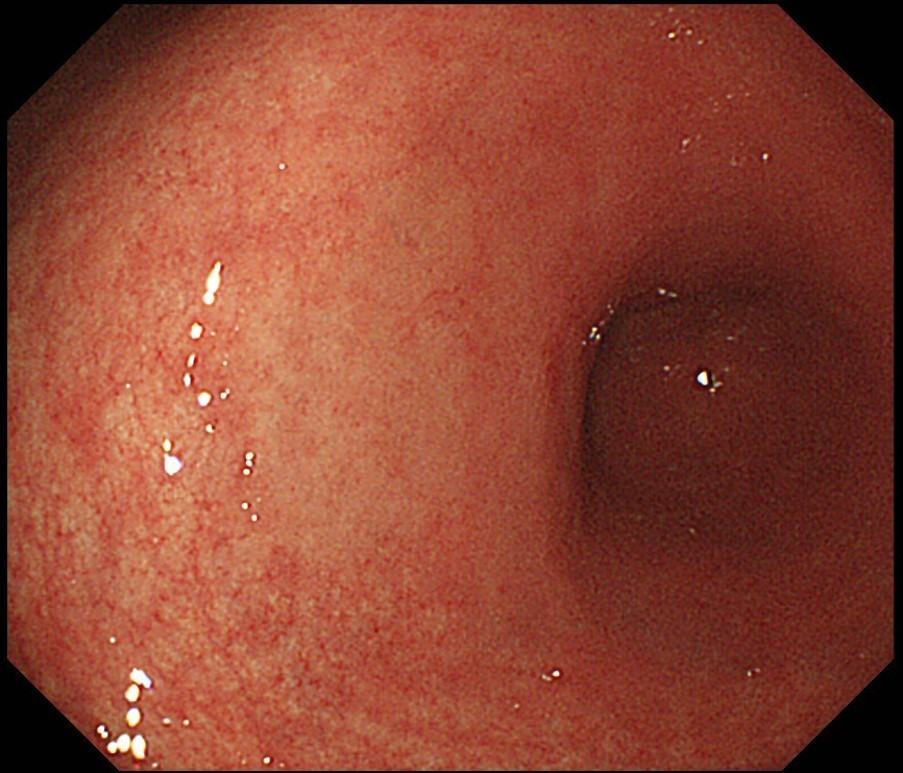

このような症状があるかたは、大腸ポリープや大腸がんが原因であったり、潰瘍性大腸炎/クローン病といった腸の炎症による病気が原因であることがあります。 もちろん痔(内痔核)などの良性疾患が原因のこともありますが、最近は年齢が若い方で大腸がんが見つかり治療が必要な方もいます。

早期発見であれば内視鏡治療によりおなかを切らずに治療することができる可能性が高くなります。上記のような症状が続く方には検査をお勧めします。